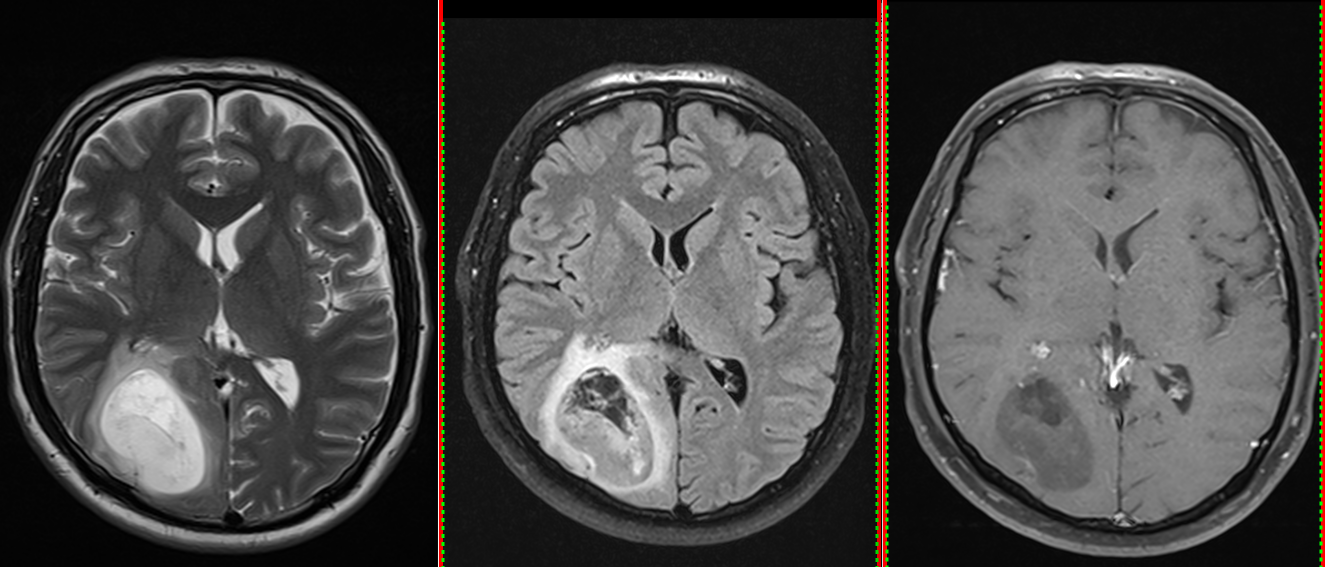

Astrocitom anaplazic (grad III) temporal drept – RMN preoperator

Astrocitom anaplazic (grad III) temporal drept – RMN postoperator

• Rezecția chirurgicală cât mai extinsă este prima etapă. Obiectivul este îndepărtarea maximă a tumorii fără afectarea funcțiilor neurologice.

• Uneori este imposibilă rezecția completă, mai ales în zone elocvente (motorii, de limbaj).